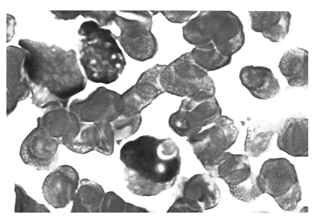

2. 检验 (1)血常规:白细胞(WBC) 3.9×109/L;血红蛋白(HBG) 136g/L;红细胞(RBC) 4.73×1012/L;血小板(PLT) 29×1012/L,血片中检见幼稚细胞;(2)骨髓像:早幼粒细胞占0.825。细胞大小不一,外形不规则,细胞浆中充满大小不等的异常颗粒,以粗颗粒为主,有的细胞内见条索状长短不一、粗细不一、多少不一的Auer小体。其排列呈散在分布,并非似柴捆样。另还可见浆中含数量不等、大小不一的红色园形小体(多则数个,少则1个,约20%的细胞内有)。见 图8~15;(3)组化染色:过氧化酶(POX)染色:呈强阳性,红色小体被黑色染料覆盖。见 图6~7;非特异性酯酶染色(α—NBE)染色:阴性,胞浆可见清晰、有透明环围着的无色小体。见 图1~3;特异性酯酶染色(AS—DNCE)染色:阳性,胞浆上可见明显比浆更红的园形小体。见 图4~5;(4)免疫学检查骨髓过氧化物酶:(MPO)、CD33阳性,CD34及人类白细胞抗原(HLA-DR)阴性;(5)遗传学检查:特异染色体易位t(15;17)(q22;q12-21)及形成融合基因(PML-RAR)。

据报道,APL早幼粒细胞可见浆中颗粒粗大,密集或融合。染深此紫红色,可掩盖核周围甚至整个胞核[ 1]。APL型早幼粒细胞超微结构显示,胞浆内核糖体丰富,高尔基复合体发达,粗内质网增高,大部分扩大,且充满着无定形物质。胞质初级颗粒生成异常,颗粒生成亢进而大量聚积,颗粒的大小,形态和内部结构不一致性,以及颗粒异常融合形成大的Auer小体[ 2]。曾有报道:APL型早幼粒细胞浆内检见透明长条状物体,粗细不一,长短不一,数量不定、排列不整齐,少数覆盖在核上。我们所见的红色园形小体不透明,大部分分布在胞浆内,偶见覆盖在核上。组化染色结果显示与浆染色结果相同。同时Auer小体出现的数量比园形小体要少,其形态长短粗细不定[ 3]。本片中白血病细胞有胞浆中红色园形小体出现还未曾见报道。这种红色园形小体在胞浆内大量出现,是否是胞浆内核糖体、高尔基复合体,粗面内质网达到一个质和量的极至,造成初级颗粒生成亢进聚积而形成是我们的一个推测。专家认为小体可能是早幼粒细胞吞噬异物(细胞碎片或细菌等)而形成。这有待进一步探讨。